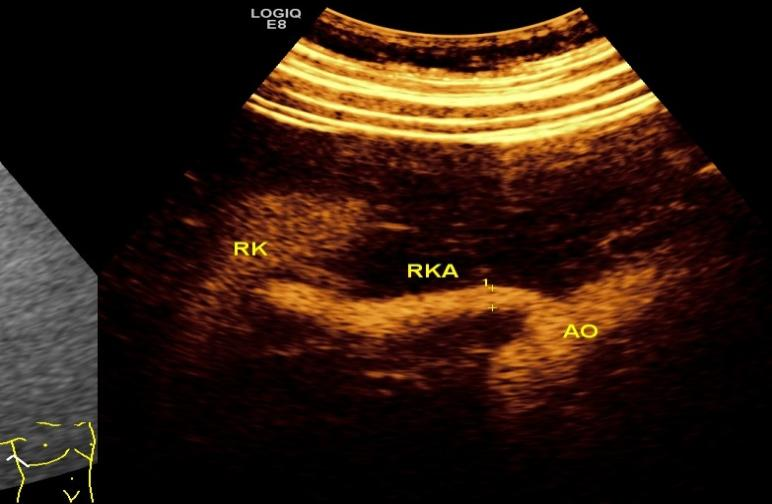

2   超声造影:显示右侧肾动脉弥漫性重度狭窄